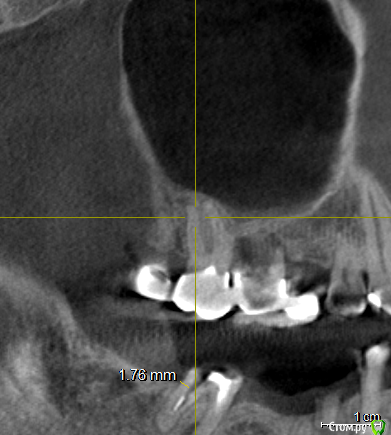

vpaoli Опубликовано 29 февраля, 2016 Поделиться Опубликовано 29 февраля, 2016 (изменено) Посыпались зубы... , что говорят имплантологи-хирурги известно - все удалить и заменить. Хотелось бы получить мнение терапевтов.Под вопросом зубы 16-17, 26-27 и 47. С 45-47 слетел мост, 26-27 после чистки ниткой, у нитки гнилостный запах, над ними в гайморовой пазухе большая киста (видимо как говорят стоматологи онтодогенного происхождения). 47 сидит очень крепко, красноватого цвета, видимо резорцированный и хрупкий. подскажите, можно ли хоть какой то из них лечить?Еще вопрос - над 26, 27 киста в гайморовой пазухе, это опасно или лучше не трогать ? О кисте я узнал только сделав КТ, ранее и сейчас даже не ощущаю ее присутствие.Всех заранее благодарю за высказанное мнение. Изменено 29 февраля, 2016 пользователем vpaoli Ссылка на комментарий

DmitrySH Опубликовано 1 марта, 2016 Поделиться Опубликовано 1 марта, 2016 Что-то КТ скачалось, но при установке ошибку выдает. По этим скринам, 45 точно удаляется. Это без вариантов. У меня есть некоторые сомнения в 4716 да, возможно удаление, но ракурс не очень удачный. ради него и хотел КТ посмотреть.18. не будет функционировать как зуб.Про мост 47-44 лучше сразу забыть и планировать имплантацию в обл 46, 45. 1 Ссылка на комментарий

vpaoli Опубликовано 3 марта, 2016 Автор Поделиться Опубликовано 3 марта, 2016 (изменено) Еще небольшой вопрос - что же мне делать с 45-47. Думаю ставить мост на имплантах 45-47 ( 46 искуccтвенyый) . Почему мост ? Потому, что 46 нет давно и альвеолярный отросток в этом месте имеет вверху острый угол т.е. нужна тоже пластика кости, а это дополнительные деньги и "страдания моего организма" (высокая температура и др. риски). У меня под 45 внутри дырка после резекции верхушки корня с выходом на край альвеолярного гребня на сторону щеки, я это место даже при надавливании пальцем чувствую, в этом месте раньше был свищь. Т.е. вкручивать имплант особо некуда. По моим соображениям для 45 существует 2 альтернативных решения: 1) заполнение этой дырки и лунки костным материалом и через 4 месяца сверление в этом месте под имплант; 2) удаляется зуб и сразу вставляется имплант вместе с куском моей аутокости на границу гребня со стороны щеки или еще как то ...Я склоняюсь к 1) т.к. никуда не спешу и желаю надежности .Правильно я понимаю, что 2) гораздо дороже по деньгам и ничуть не надежнее, чем 1) ? Изменено 3 марта, 2016 пользователем vpaoli Ссылка на комментарий